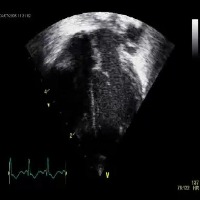

Healthcare and Medical Diagnostics: Utilize the "opt_subopt" model to analyze and categorize ultrasound images, helping medical professionals identify normal, abnormal, and suboptimal cases for better diagnosis and treatment planning.

Medical Education and Training: Integrate the computer vision model into medical education software and simulation tools, enabling students and healthcare practitioners to improve their skills in identifying and understanding different A4C classes in ultrasound images.

Quality Assurance for Ultrasound Equipment: Employ the "opt_subopt" model to evaluate the performance of ultrasound devices by identifying images with A4CSuboptimal and A4CAbnormal results, providing feedback to manufacturers for device improvements and maintenance.

Ultrasound Image Curation and Database Management: Implement the computer vision model in organizing large collections of ultrasound images based on their A4C classes, aiding researchers in finding specific categories of images more efficiently for their studies.

Telemedicine and Remote Consultations: Integrate the "opt_subopt" model with telemedicine platforms, allowing healthcare providers to review and analyze ultrasound images remotely and offer guidance to frontline staff in real-time based on the identified A4C classes.